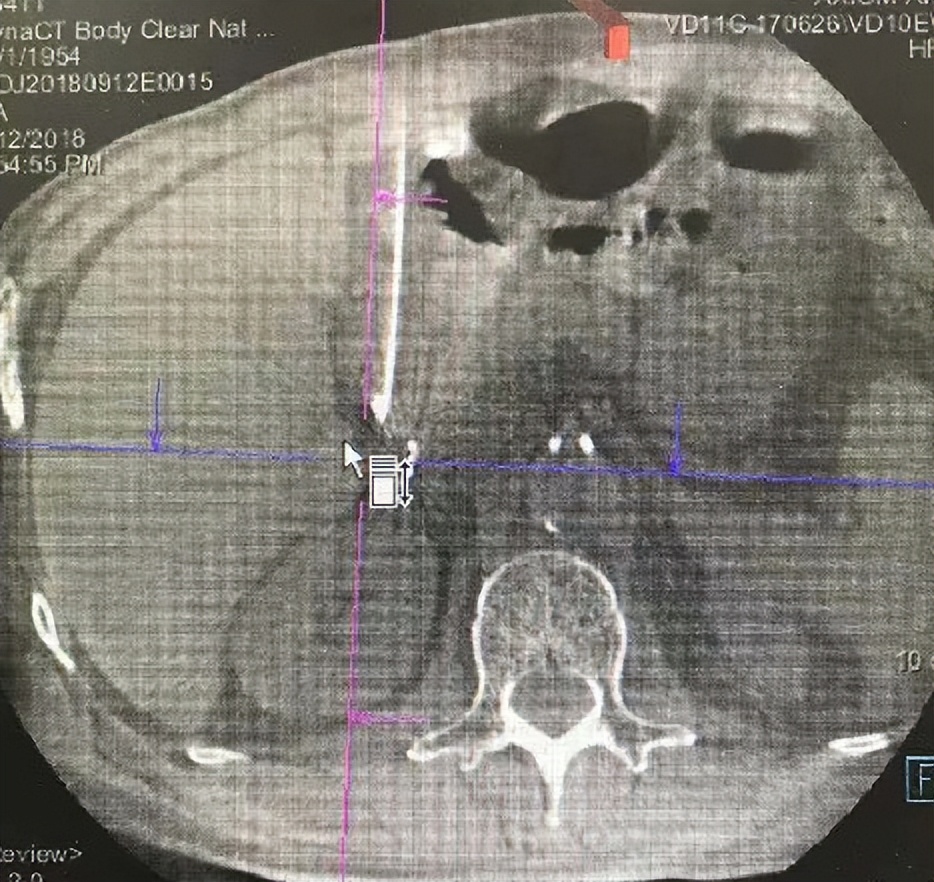

DynaCT导向下,采用粒子植入针,经皮、经胃穿刺至靶肝门部淋巴结。

穿刺到位后,根据内放疗计划,透视下植入放射性粒子15颗。